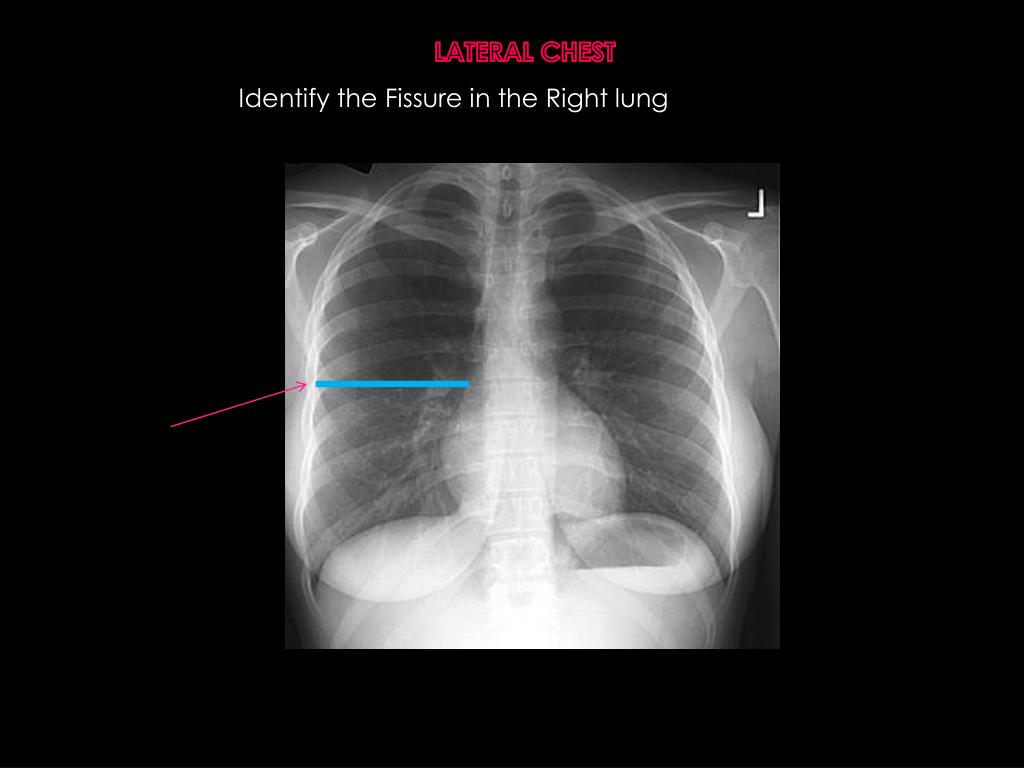

21. LATERAL CHEST Identify the Fissure in the Right lung

22. LATERAL CHEST Identify the Fissure in the Right lung Horizontal/minor fissure